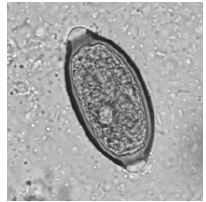

Durante um exame parasitológico de fezes você avistou a seguinte estrutura:

Enunciado 2640265-1

Fonte: Atlas de parasitologia clínica - www. parasitologiaclinica.ufsc.br

Ao reportar o laudo, você deve afirmar a presença de ovos de qual parasita?